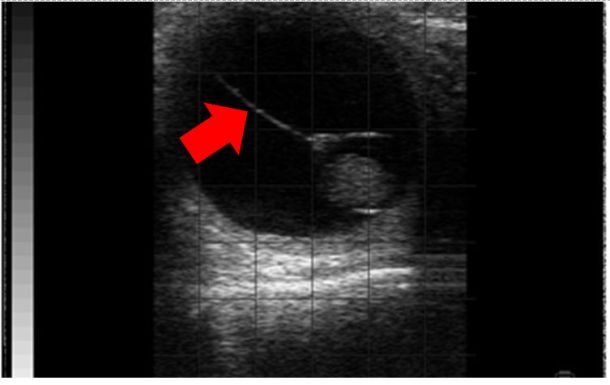

Twinning is an undesirable trait in cows as it will increase the risks of abortion, dystocia, retained placenta, endometritis and it will reduce subsequent fertility8. In Ireland, approximately 1.74 per cent of all calves born tend to be registered as twins but in the region of 6.83 per cent of cows will have double ovulations9. The vast majority (>90-95 per cent) of twins are dizygotic, arising from two oocytes from double ovulation8. Twins are best diagnosed from 30-80 days of gestation and, to be absolutely sure, both embryos must be clearly observed2,8. After 80-100 days, visualising both becomes more challenging a task and can lead to them being missed. As twins arise from double ovulations, checking the ovaries for two CLs is a useful task but beware that it can lead to both false positives (a cow with a single calf can be diagnosed with twins as she has two CLs) and false negatives (a cow is not diagnosed with twins as she has only one CL). Twins can be located in one horn (unilateral) or two horns (bilateral) and as transuterine migration in cows is rare, unilateral instances arise from a double ovulation on a single ovary while bilateral arise from a single ovulation on both ovaries2,8. Unilateral twins tend to be a bit more common (~56 per cent) versus bilateral (~44 per cent) but unilateral twins will have much higher rates of pregnancy loss (mid-to-late gestation loss of one per cent versus 40 per cent)8. In unilateral twin pregnancies, a traceable hyperechoic (white) line from embryo to embryo – the so-called ‘twin’ line (see Photo 4) which represents the area of apposition between the two chorionic membranes – is a useful additional tool to aid in diagnosis8.